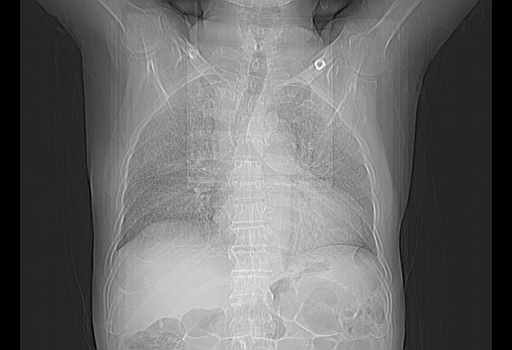

胸腹部CT,诊断意见:左上肺叶钙化灶、左侧胸膜局限性增厚并钙化、胆囊炎。描述部分肺组织呈磨玻璃样改变。